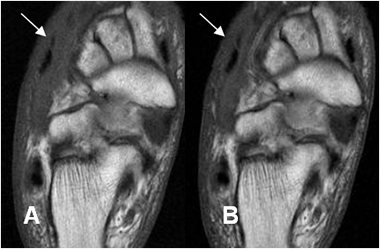

Fig 126 A. Pie diabético.

A: Rx AP y B: Rx oblicua del pie. Ausencia de las falanges del 4º y 5º dedo, por amputaciones previas. Calcificación en las paredes de los vasos, por angiopatía diabética. (Flechas).

Fig 126 B. Pie diabético. Osteomielitis.

A: RM coronal en T1 y B: RM coronal en STIR. Osteomielitis del 4º metatarsiano hipointenso en T1 e hiperintenso en STIR (Punta de flecha), con cambios inflamatorios en los tejidos blandos. (Flechas delgadas). También hay cambios inflamatorios en el dorso del pie y sobre el 1º dedo. (Flechas gruesas).